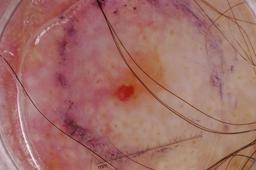

{

"age_approx": 40,

"anatom_site_general": "lower extremity",

"concomitant_biopsy": true,

"dermoscopic_type": "contact non-polarized",

"diagnosis_1": "Benign",

"diagnosis_2": "Benign melanocytic proliferations",

"diagnosis_3": "Nevus",

"diagnosis_confirm_type": "histopathology",

"image_type": "dermoscopic",

"lesion_id": "IL_0404349",

"melanocytic": true,

"sex": "female"

}